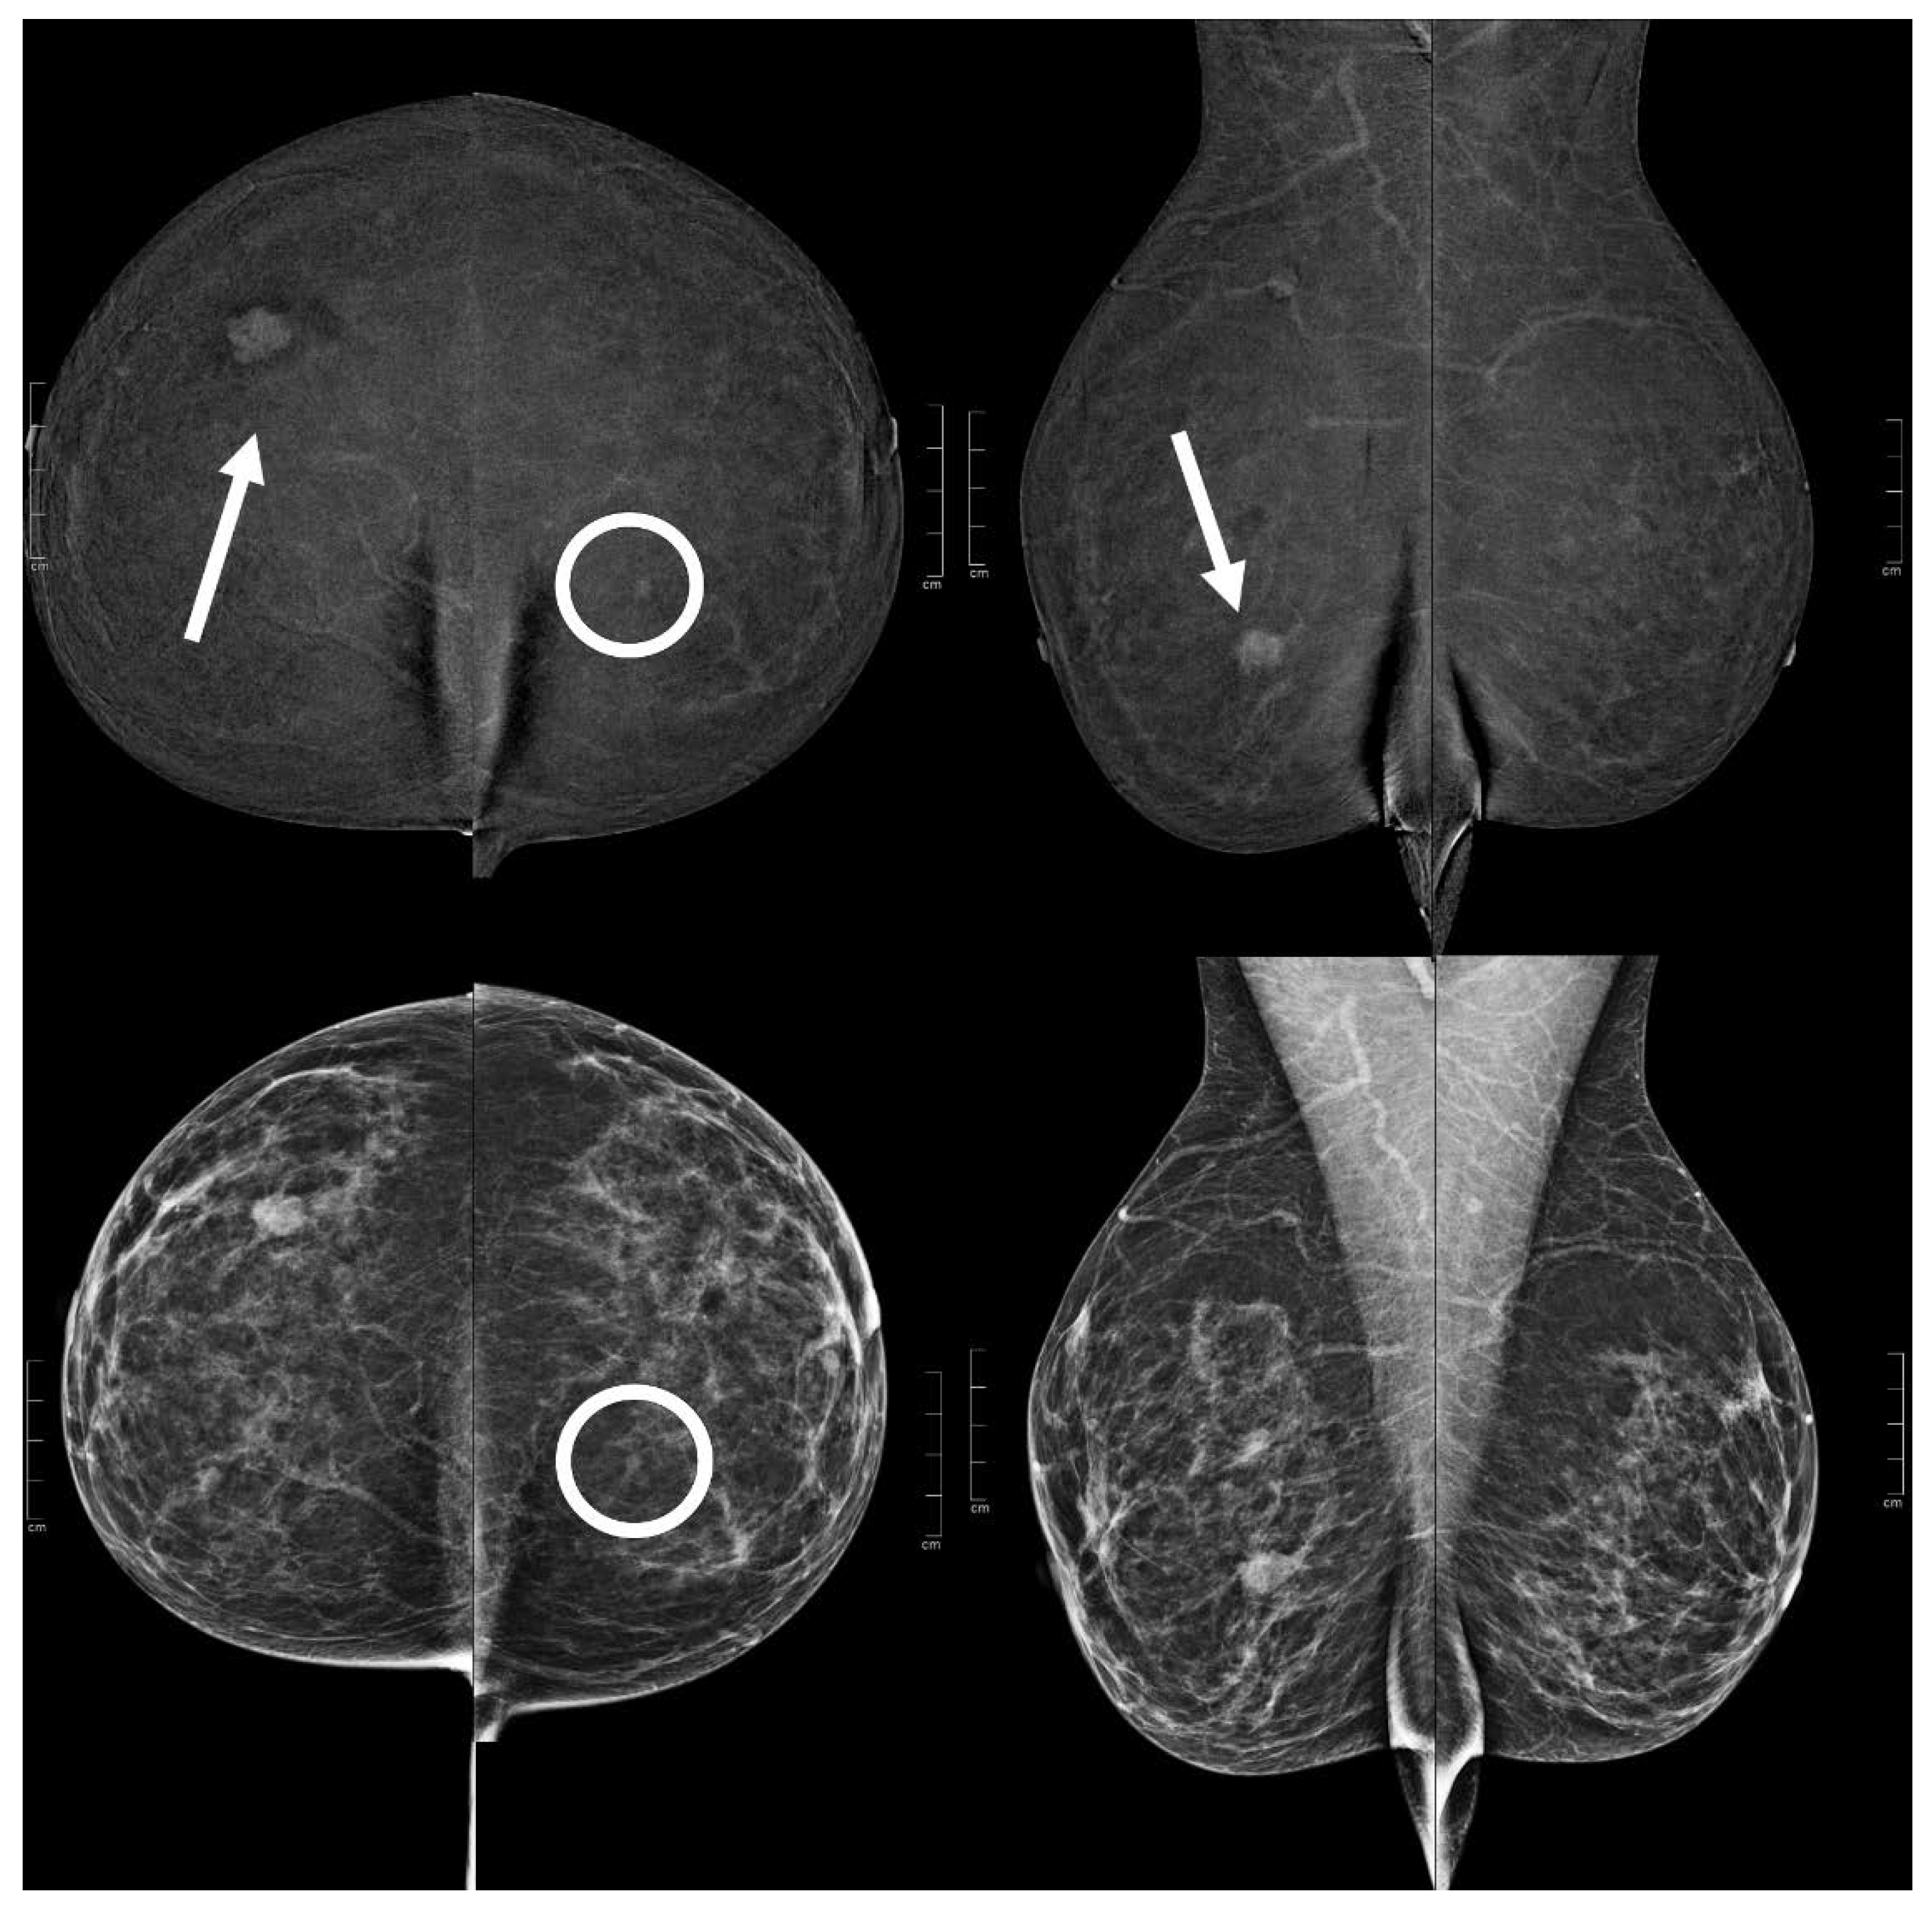

Figure 5.

A 51 year old patient. Contrast-enhanced digital mammography performed as preoperative staging for a B5 lesion in the right breast (arrows). In the early RC in the left breast, there was an enhancing asymmetry in the inner quadrants with moderate conspicuity only visible in CC (circle), corresponding to an opacity in low-energy images. This opacity subsequently underwent VABB (tomosynthesis-guided vacuum assisted breast biopsy), which confirmed an invasive carcinoma.

Figure 6.

A 60 year old patient. Contrast-enhanced digital mammography performed as preoperative staging for a B5 lesion in the left breast (arrows). In the early RC in the right breast, there was an enhancing asymmetry in the central quadrants with high conspicuity only visible in CC (circle), corresponding to an architectural distortion in low-energy images. This architectural distortion subsequently underwent VABB (tomosynthesis-guided vacuum assisted breast biopsy), which confirmed a ductal in situ carcinoma.